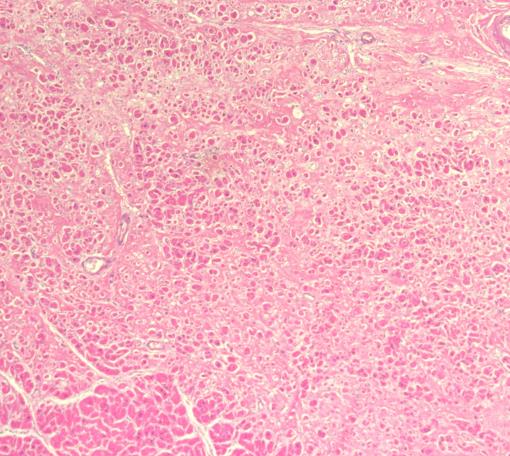

镜检:心脏轻度自溶。心肌纤维粗细不一,部分拉长变细,以乳头肌为甚,部分呈不规则波浪状排列,心肌间纤维组织增生和脂肪组织浸润,心肌被分隔为条索状,局部心肌纤维嗜伊红染色增强,部分横纹消失,部分心肌细胞核消失。窦房结纤维组织增多,结细胞减少,纤维化程度>75%,窦房结和房室结与束支内见脂肪细胞浸润。

根据检验情况,结合病史资料及案情调查,被鉴定人孙某某2021年10月24日乘坐三轮载货摩托车(后座)发生交通事故,当即意识丧失、呼吸心跳骤停,120急救人员到达现场时被鉴定人孙某某已无自主呼吸、大动脉搏动消失,予心肺复苏,至急诊时神志昏迷,双瞳散大、均无光反射,颈动脉无搏动,生理反射消失,紧急抢救后恢复自主心率,无自主呼吸、气管插管、转运呼吸机控制通气,生理反射、病理反射均未引出。既往有胸闷心慌病史。查体深昏迷,GCS评分E1VTM1。CT检查颅内未见明显异常,两肺上下叶局限性炎症、双侧胸膜局限性增厚等。心电图(复苏后)示窦性心动过速、完全性右束支传导阻滞、ST-T段改变。入院予亚低温脑保护、机械通气、脱水减轻脑水肿、升压、营养神经、维持内环境稳态、护胃、祛痰、支持等治疗。出院时被鉴定人孙某某高热、无自主呼吸、气管插管机械通气、去甲肾上腺素、肾上腺素泵入升压,冬眠合剂持续泵入降温。深昏迷,生理反射、病理反射未引出。出院后死亡。尸检见头皮下出血(右额部),余未检见明显异常改变。组织学检见窦房结纤维组织增多,结细胞减少,纤维化程度>75%,窦房结和房室结与束支内见脂肪细胞浸润,符合心传导系统纤维化、脂肪浸润病理组织学改变;广泛细支气管及其周围肺泡腔内充满以中性粒细胞为主的脓性渗出物,部分支气管上皮细胞脱落,尚见少量红细胞(以双肺下叶为甚),符合肺部感染病理组织学改变;另检见多脏器缺血、缺氧等改变。综上检验情况:1.尸体检验被鉴定人孙某某头皮下出血,余未检见致死性外伤,交通事故不足以直接致其死亡;2.根据组织学检验,被鉴定人孙某某心脏重357g(正常成年女性240g-260g),镜检见心脏传导系统纤维化、脂肪浸润,余未检见其他致死性疾病改变。结合复苏后心电图诊断,分析认为,被鉴定人孙某某符合自身罹患心脏传导系统纤维化、脂肪浸润等病变基础上突发心律失常致心跳骤停、多脏器缺血、缺氧继发肺部感染死亡。心律失常常因精神高度紧张或情绪激动等而发作,突发交通事故可诱发其心律失常的发作。

窦房结镜下情况

房室结镜下情况